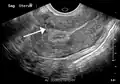

Diagnosis

Physical examination and ultrasound are sufficient for diagnosing uterine fibroids in the majority of patients. When ultrasound findings are inconclusive, magnetic resonance imaging (MRI) may be able to confirm the diagnosis of uterine fibroids in most cases. In addition, MRI can identify benign uterine fibroids with atypical imaging features and fibroids with variant growth patterns. MRI can also identify other uterine (e.g. adenomyosis, endometrial polyps, endometrial cancer) and extrauterine (e.g. benign and malignant ovarian tumors, endometriosis) disorders that may mimic the appearance of uterine fibroids and/or contribute to the patient's symptoms.[37] However, a small proportion of uterine fibroids can mimic other malignant uterine tumors (e.g. leiomyosarcoma) on all available imaging modalities (e.g. ultrasound, CT, MRI and PET-CT).[37]

Malignant tumors of the uterine wall (e.g. leiomyosarcoma) are very rare. Findings suggestive of a malignant uterine tumor rather than a benign fibroid include, fast or unexpected growth (particularly after menopause), interruption/effacement of the endometrial stripe, lymph node enlargement, invasion of adjacent organs and metastases to distant organs (e.g. lung). MRI findings suggestive of a malignancy include nodular/ill-circumscribed tumor margins, intermediate/high T2-weighted signal intensity of the solid tumor components, regions with high signal T1-weighted sequences in keeping with subacute hemorrhage, fine/wispy enhancement of the solid parts of the tumor, and restricted diffusion on diffusion-weighted imaging (DWI).[37] A biopsy is rarely performed and if performed, is rarely diagnostic. Should there be an uncertain diagnosis after ultrasounds and MRI imaging, surgery is generally indicated.[38]